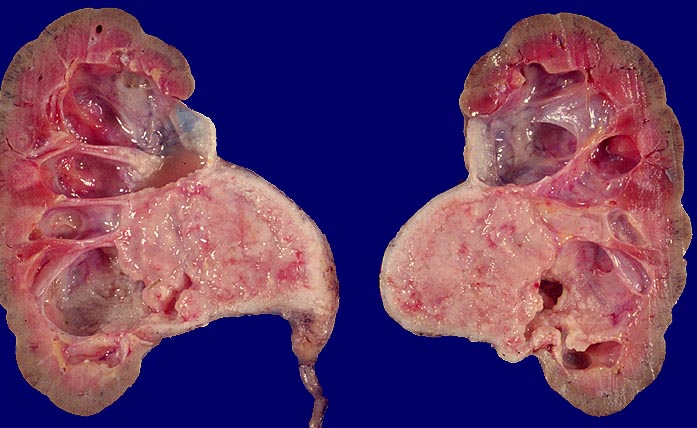

Morphologie:

Pathomorphologisch unterscheiden sich Urothelkarzinome bei Phenacetinabusus nicht von sporadischen Urothelkarzinomen abgesehen von ihrer bevorzugten Lokalisation im Nierenbecken und der allenfalls ausserhalb des Tumors in der Harnwegsschleimhaut nachweisbaren Kapillarosklerose.

Morphologische Merkmale:

• Solider Tumor mit fokalen Entzündungsinfiltraten.

• Polymorphe Tumorzellen mit unscharfen Zellgrenzen und bläschenförmigen (=vesikulären) Kernen.

• Zahlreiche Mitosen.

• Ureter mit verdickten Kapillaren (Kapillarosklerose).